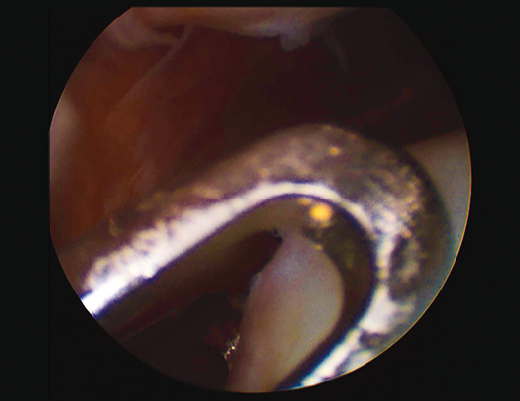

First surgery involves arthroscopy of the damaged joint. It assesses the chondral lesion to be treated and confirms whether it is amenable to the chondrocyte implantation technique (Figures 1 and 2). Other procedures are also carried out if needed, such as for example reconstruction of the anterior cruciate ligament, partial meniscectomies, meniscus implantation, patellar realignments, osteotomies, etc. Lastly, the cartilage sample is taken from a non-weight bearing zone (intercondylar zone or internal femoral condyle at its upper margin). The sample is extracted with biopsy forceps or, alternatively, using discectomy forceps. Between 3-4 rice grain-sized fragments of healthy cartilage are harvested (Figure 3). The biopsy material is placed in a sterile receptacle containing a culture medium (DMEN) (Figure 4). The material is kept at room temperature and is shipped to the laboratory as quickly as possible. A form should be completed (Figure 5), stating the joint, the location of the lesion and the size of the defect. Once in the laboratory, the sample is processed and cultured. After 4-6 weeks (depending on the case), the culture is ready for implantation.